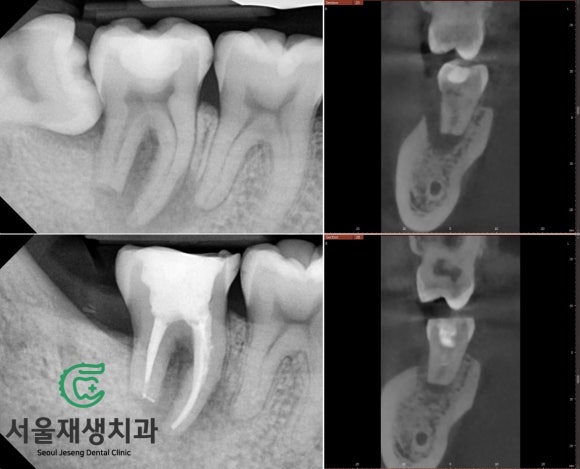

[치료사례] 고난이도 신경치료 (뿌리가 흡수된 치아의 신경치료, 서울재생치과)

#신경치료 #미세현미경신경치료 #자연치아살리기 #치과보존과전문의 #신촌치과 #신촌서울재생치과